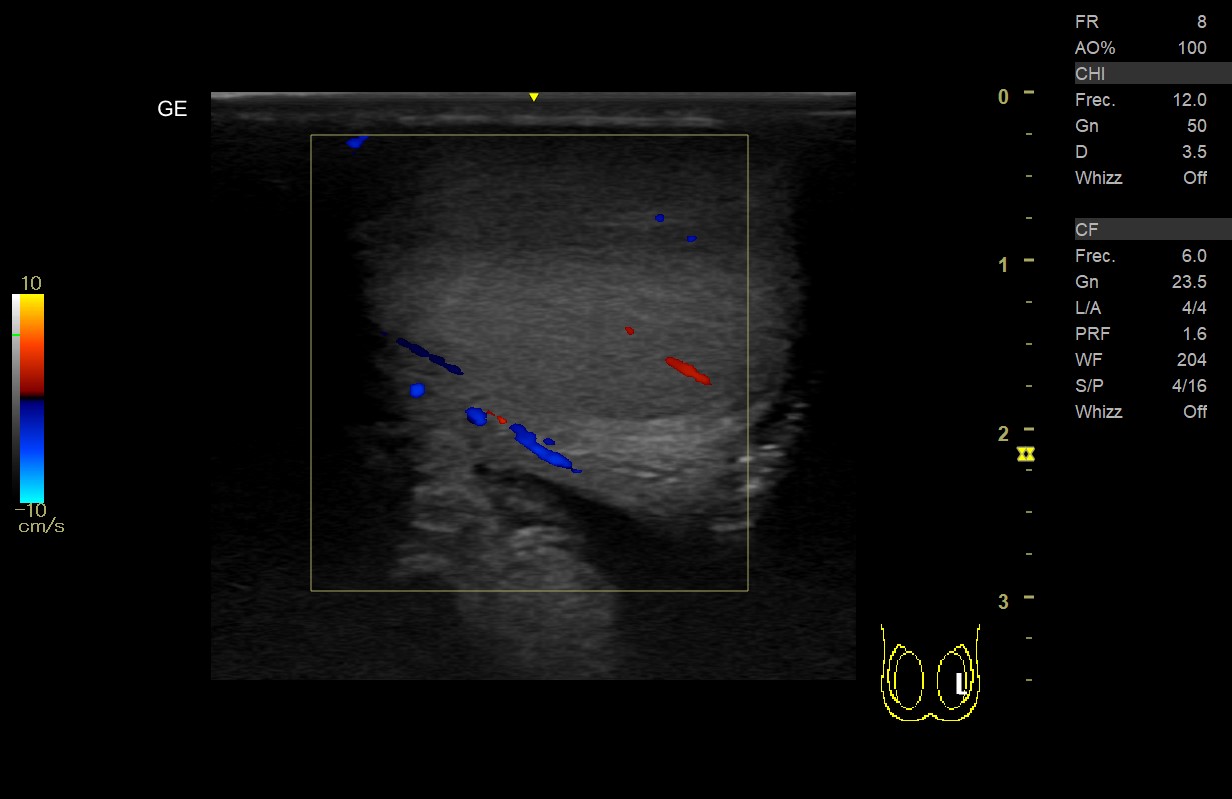

• Teste derecho: aumento de volumen con ecogenicidad heterogénea (áreas más hipoecogenicas), sin captación Doppler color ni power en teste o epidídimo derecho y presencia de líquido en bolsa escrotal.

• Teste izquierdo: volumen y ecogenicidad homogénea con captación Doppler en teste y epidídimo, ausencia de hidrocele.

Al realizar la ecografía, destaca la ausencia de captación Doppler lo cual nos inclina a un diagnóstico de Torsión testicular, ya que a nivel ecográfico la epididimitis presentaría una mayor vascularización y flujo con Doppler.